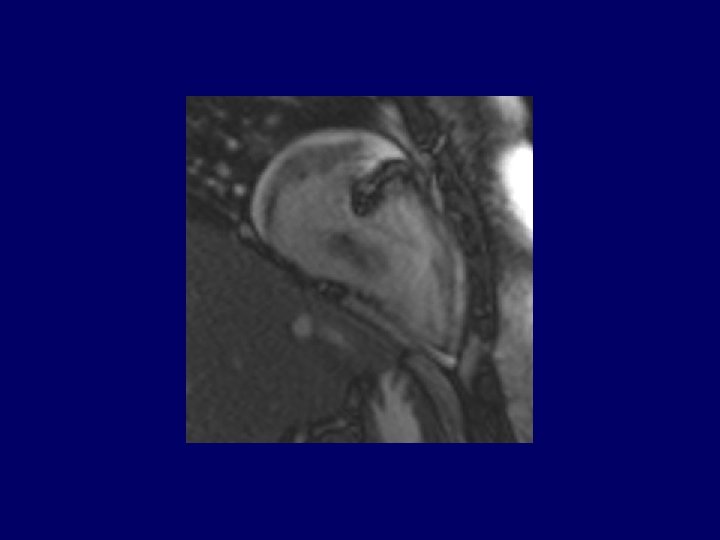

MRI Images

T 1 -pre T 1 -post T 2 -pre T 1 -IR-delay post

Evaluation of cardiac mass On cardiac MRI, avascular masses (thrombus) can be differentiated from tumors as they appear hypointense in T 2 weighted images and do not enhance with contrast. Differentiating between thrombus and vegetations from tumors using noninvasive means is crucial as it may determine the need for and timing of resection.